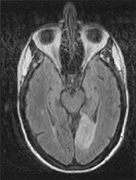

Achromatopsia in the contralateral hemifield alone can follow unilateral right or left occipital lesions (Fig. 18). Patients are typically asymptomatic until the defect is demonstrated on examination.234,235 Hemiachromatopsia is usually associated with a superior quadrantanopia;234,235,241 therefore, the color defect is only demonstrable in the remaining inferior quadrant. The preserved color vision in the ipsilateral hemifield allows normal or near-normal performance on centrally viewed tests of color vision such as pseudoisochromatic plates. The incidence of hemiachromatopsia is probably underestimated, given its asymptomatic nature and the failure of routine clinical color tests to detect its presence.

Fig. 18. Magnetic resonance imaging scan of patient with stroke causing a right hemiachromatopsia as well as partial superior quadrantanopia.